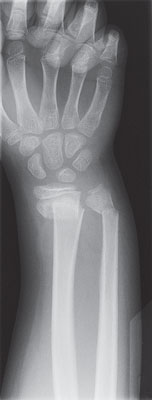

Bone X-ray

A bone X-ray is a way to take pictures of bones. It may also be called bone radiography. In this test, a low dose of radiation is passed through the body, producing digital images of the bones or images on a piece of film.

| X-ray of a broken wrist |